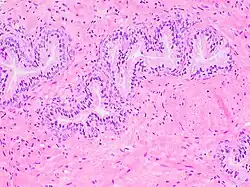

Micrograph showing normal prostate cancer in the right upper aspect of image. HPS stain. Prostate biopsy.

Prostate cancer is one of the most common cancers affecting older men in the UK, US, Northern Europe and Australia, and a significant cause of death for elderly men worldwide.[33] Often, a person does not have symptoms; when they do occur, symptoms may include urinary frequency, urgency, hesitation and other symptoms associated with BPH. Uncommonly, such cancers may cause weight loss, retention of urine, or symptoms such as back pain due to metastatic lesions that have spread outside of the prostate.[28]

A digital rectal examination and the measurement of a prostate-specific antigen (PSA) level are usually the first investigations done to check for prostate cancer. PSA values are difficult to interpret, because a high value might be present in a person without cancer, and a low value can be present in someone with cancer.[28] The next form of testing is often the taking of a prostate biopsy to assess for tumour activity and invasiveness.[28] Because of the significant risk of overdiagnosis with widespread screening in the general population, prostate cancer screening is controversial.[34] If a tumour is confirmed, medical imaging such as an MRI or bone scan may be done to check for the presence of tumour metastases in other parts of the body.[28]

Prostate cancer that is only present in the prostate is often treated with either surgical removal of the prostate or with radiotherapy or by the insertion of small radioactive particles of iodine-125 or palladium-103, called brachytherapy.[35][28] Cancer that has spread to other parts of the body is usually treated also with hormone therapy, to deprive a tumour of sex hormones (androgens) that stimulate proliferation. This is often done through the use of GnRH analogues or agents (such as bicalutamide) that block the receptors that androgens act on; occasionally, surgical removal of the testes may be done instead.[28] Cancer that does not respond to hormonal treatment, or that progresses after treatment, might be treated with chemotherapy such as docetaxel. Radiotherapy may also be used to help with pain associated with bony lesions.[28]

Sometimes, the decision may be made not to treat prostate cancer. If a cancer is small and localised, the decision may be made to monitor for cancer activity at intervals ("active surveillance") and defer treatment.[28] If a person, because of frailty or other medical conditions or reasons, has a life expectancy less than ten years, then the impacts of treatment may outweigh any perceived benefits.[28]